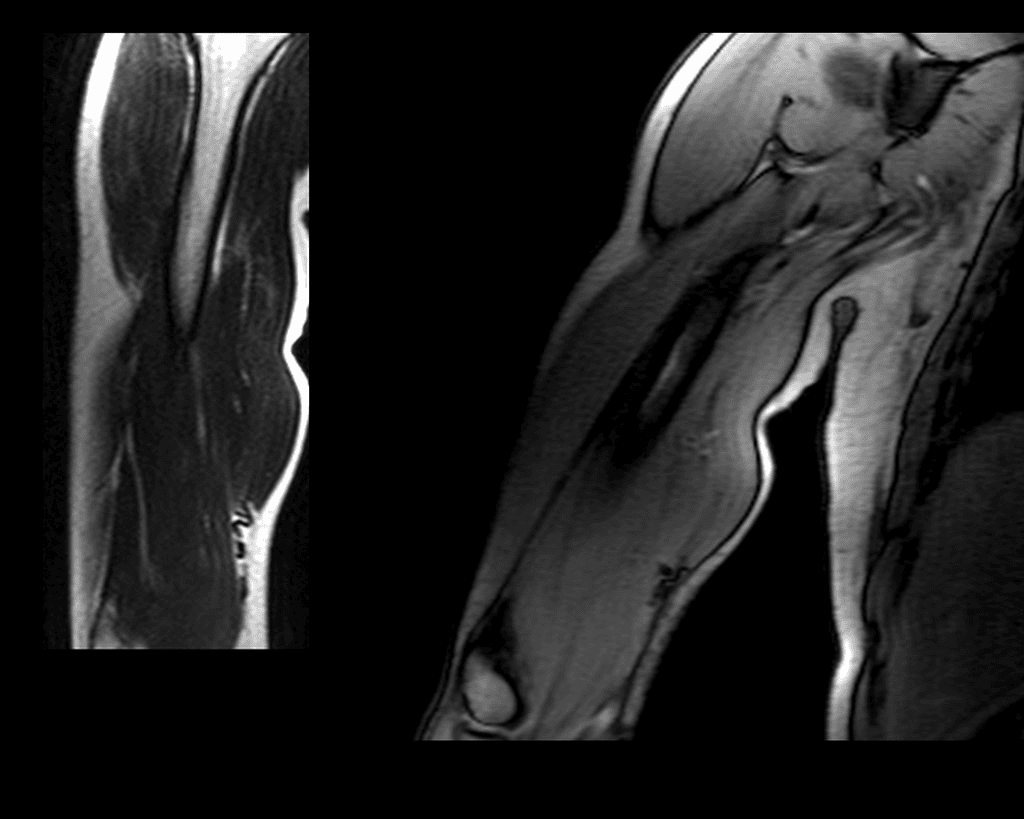

Legend Injury Update – How Gladiators Star is Recovering from Bicep Tear

‘Gladiators’ star Legend tore his bicep tendon off the bone on set. Here’s a quick recap of what happened, how the surgery went, and how he’s recovering. Gladiators’ Legend Injury: What Happened (Image Credit: Flickr) Legend, whose real name is Matt Morsia, suffered from a torn distal bicep tendon whilst tackling a contender in one … Read more